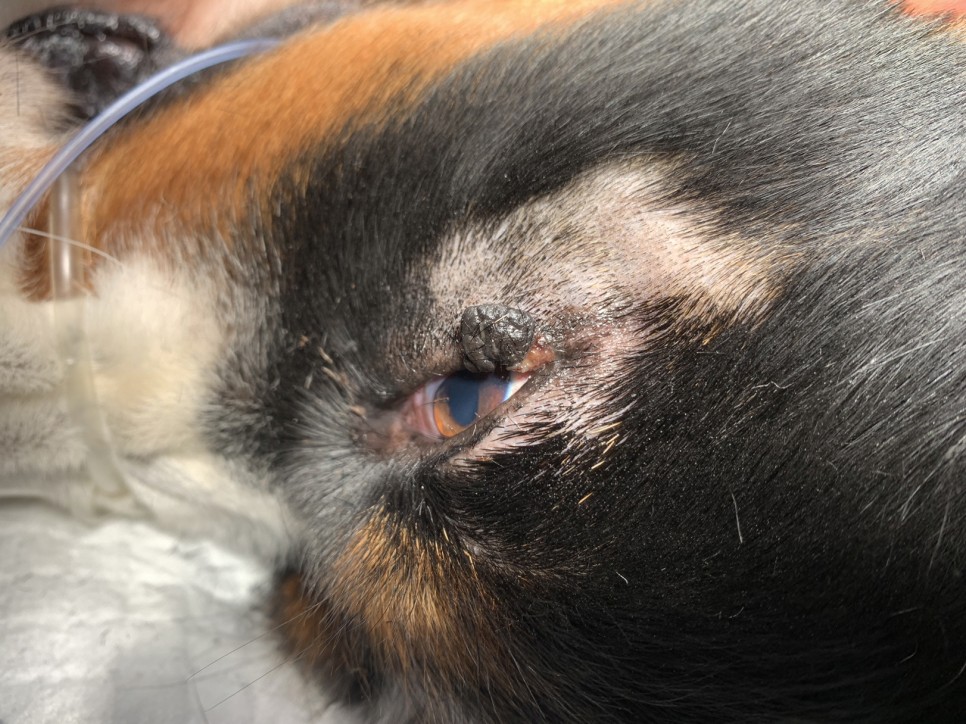

그동안 미뤄왔던 안검 종괴도 같이 제거됐습니다